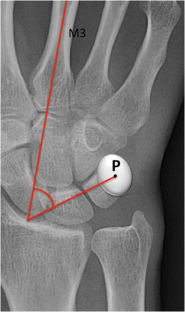

Pisotriquetral joint disorders: an under-recognized cause of ulnar side wrist pain

Pisotriquetral joint disorders are often under-recognized in routine clinical practice. They nevertheless represent a significant cause of ulnar side wrist pain. The aim of this article is to present the main disorders of this joint and discuss the different imaging modalities that can be useful for its assessment.